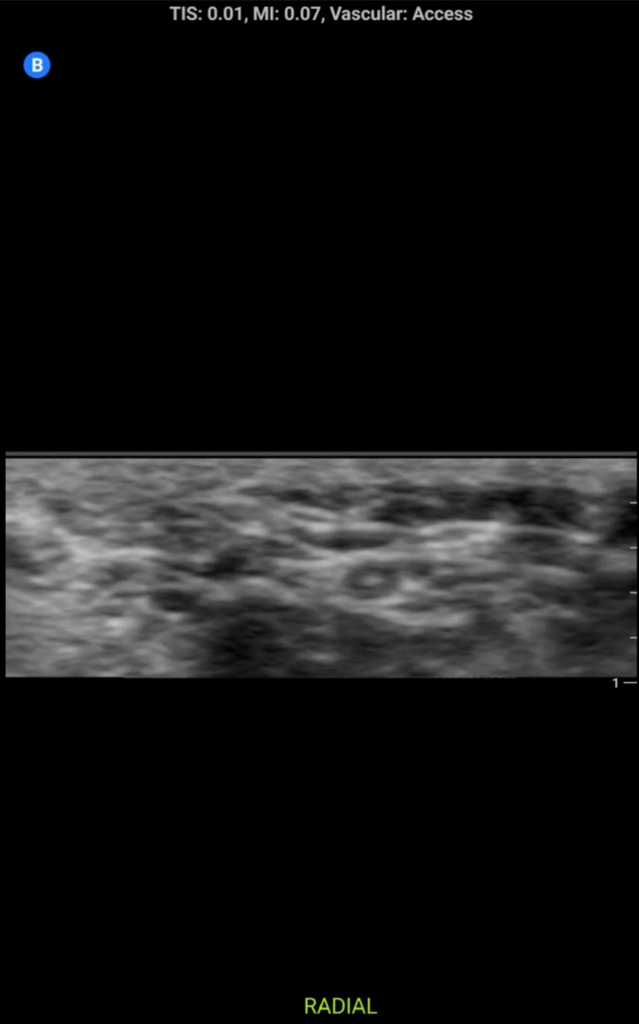

Some sample images below:

screenshot.177.pngscreenshot.178.pngscreenshot.180.pngscreenshot.179.png

View attachment 328368View attachment 328369View attachment 328371View attachment 328372